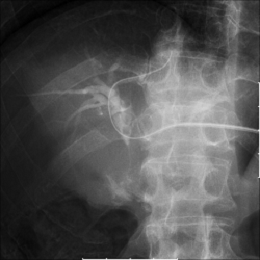

整形外科系検査

経皮的に造影剤を注入する脊髄腔造影検査(myelography)、椎間板造影検査(discography)、肩関節や手関節などの関節腔造影検査(arthrography)を行っています。また透視下で、脱臼や骨折に対して整復などの治療も行っています。